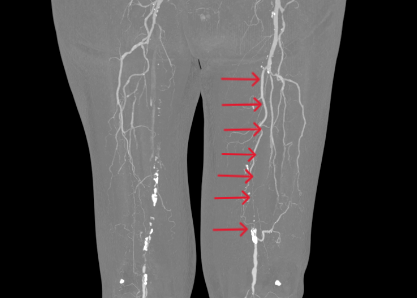

穿越无光重获行走

另一个病例中,患者病情更为复杂。术前CTA检查显示,其股浅动脉至腘动脉全程闭塞,血管外科将这种情形称为“长段无光区”。传统治疗中,开通此类如同“水泥管”般的长段闭塞血管,难度极大,术者如同在黑暗中摸索,导丝极易误入内膜下形成夹层,导致手术失败。

2.png

术中,血管外科团队以IVUS为“导航”,在其实时监视下,导丝精准找到血管真腔入口,顺利通过全程闭塞段,成功避免夹层发生,顺利打通患者腿部“生命通道”。针对血管开通后管腔内的严重增生性病变,团队采用准分子激光消融术进行减容处理,通过激光导管冷光源精准气化斑块,进一步恢复了血管正常内径。